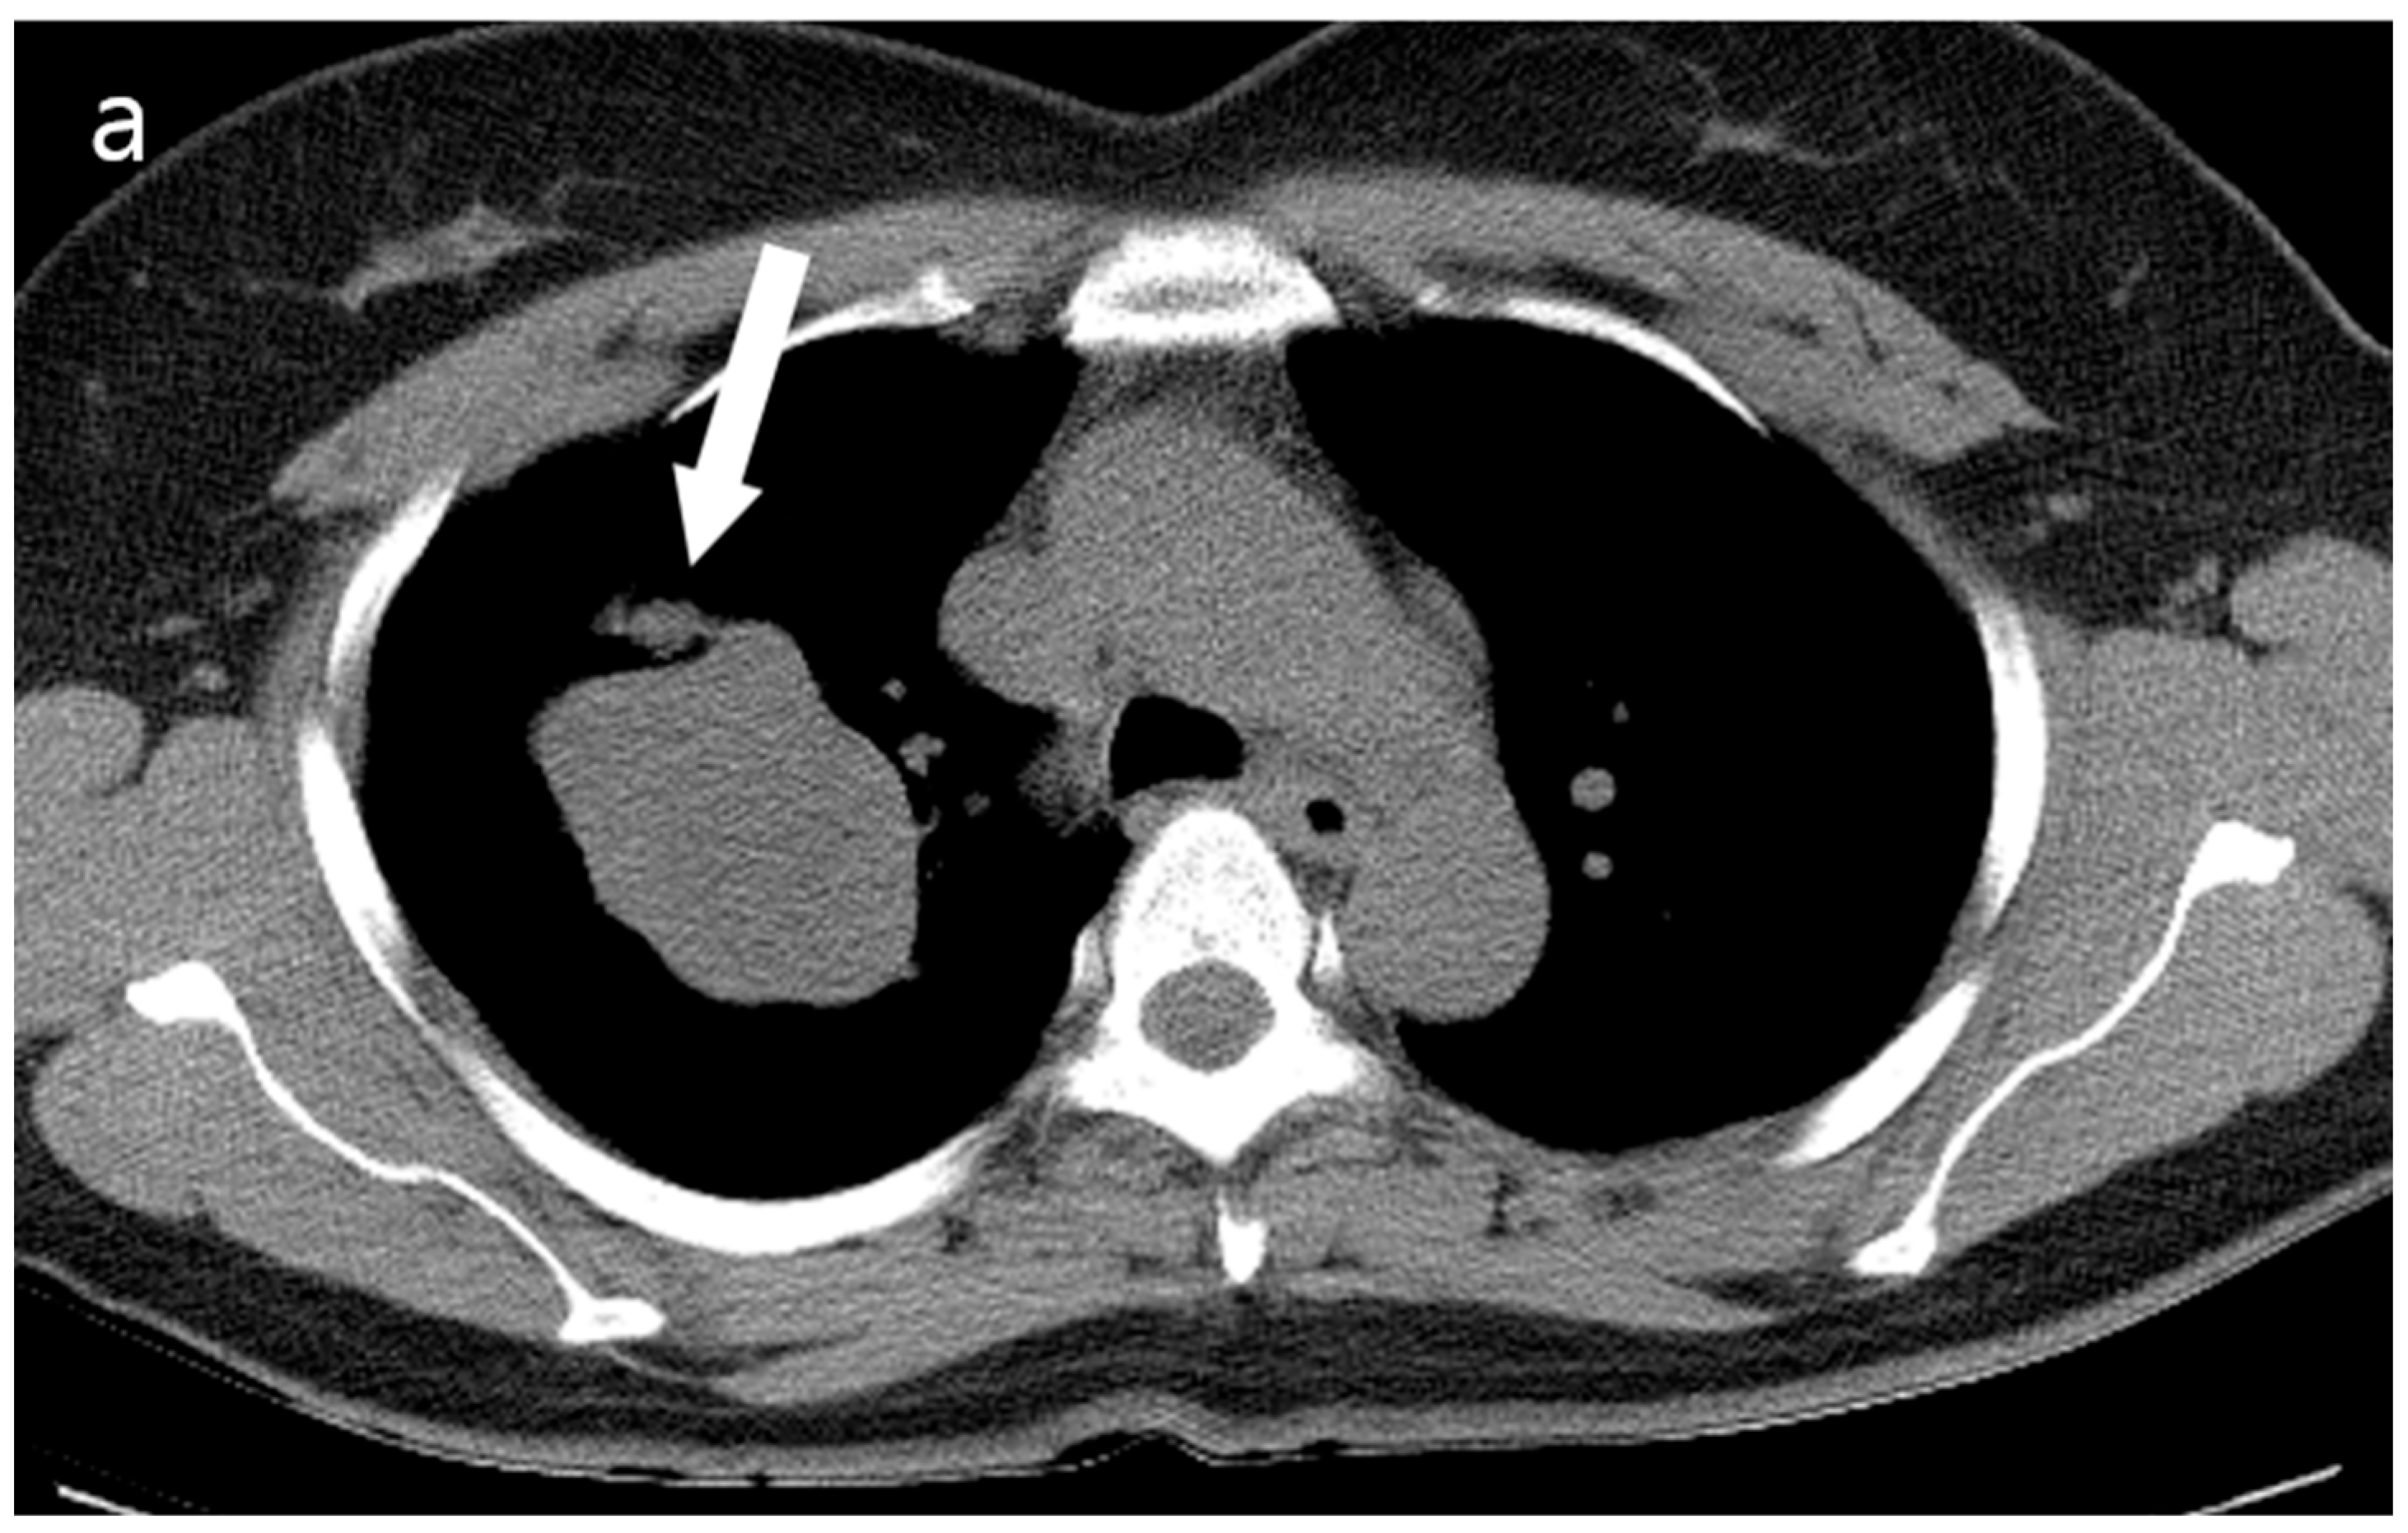

Figure 2.

(a) Unenhanced chest CT showed a homogeneous hypodense mass (5.6 cm in diameter) in the right upper lobe (white arrow). The mass had a well-defined shape with a primarily smooth, but partially beak-like lobulated margin. (b) There was splaying of the anterior and posterior segmental bronchi (black arrow) from the mass effect.